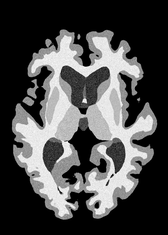

4.2 Registration to a 100 micron ex-vivo brain MRI volume

To showcase the efficacy of our method on real large scale images, we register a 250 in-vivo MRI image (Lüsebrink et al., 2017) to a 100 ex-vivo FLASH human brain volume (Edlow et al., 2019). This represents an inverse problem with more than 11.2B optimizable parameters (compared to 20M for clinical datasets), or 44.8GB of GPU memory. The entire problem does not fit on most GPUs, necessitating distributed multimodal registration. We optimize a composite transform - affine followed by a diffeomorphic mapping; details can be found in Section E.1. Multimodal deformable registration took 58 seconds on 8 NVIDIA A6000 GPUs, which is unprecedented at this resolution. Fig. 6 shows qualitative results, highlighting the ability to register highly detailed structures such as cerebellar white matter; these structures are not visible at macroscopic scales. The resultant advantages of performing registration at this scale can allow researchers to characterize the neuroanatomy at microscopic resolutions and allow morphometric analysis of cortical layers and subcortical nuclei among other structures.